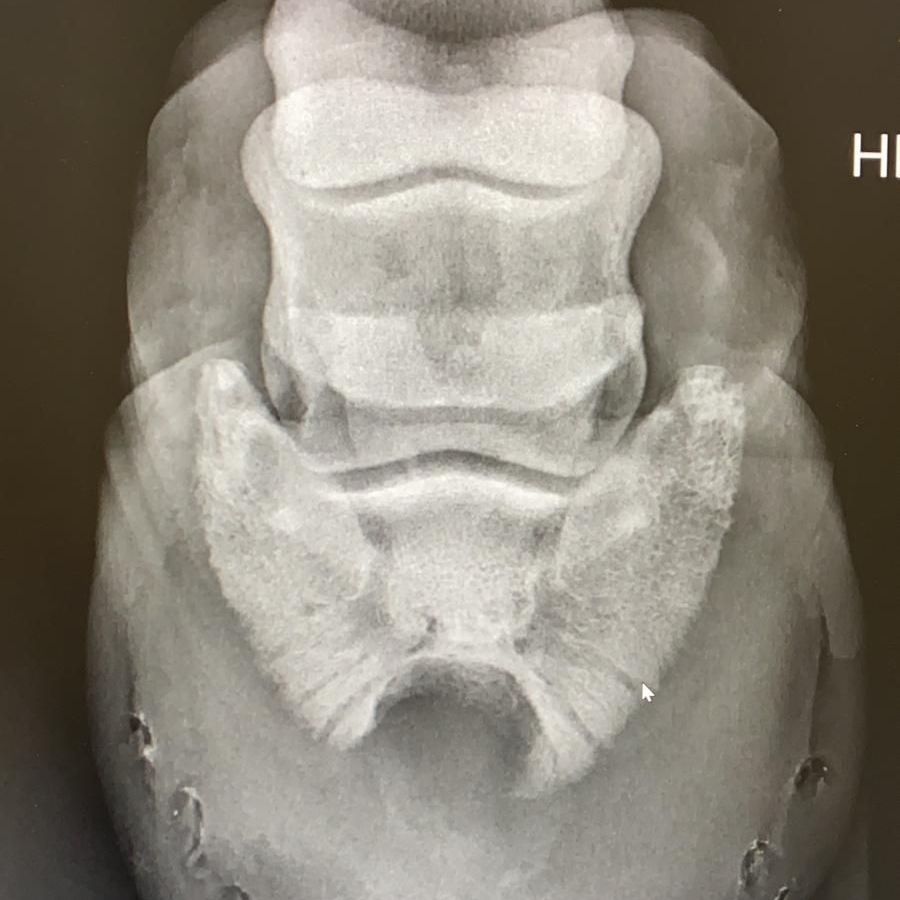

Dieses Pferd wurde vorgestellt mit ein Ruptur der oberflächlichen Beugesehne (OBS). Damit hatte das Fesselgelenk bei Belastung vom Bein Bodenkontakt.

Ein von mir etwas umgebautes Bouley-Eisen ist extrem lang. Die Länge muss bis zur Lotlinie der Hinterseite des Fesselkopfs reichen. Nur dann übernimmt das Eisen die Tragkraft des Fesselträgers, OBS und TBS und kann eine Schädigung heilen.